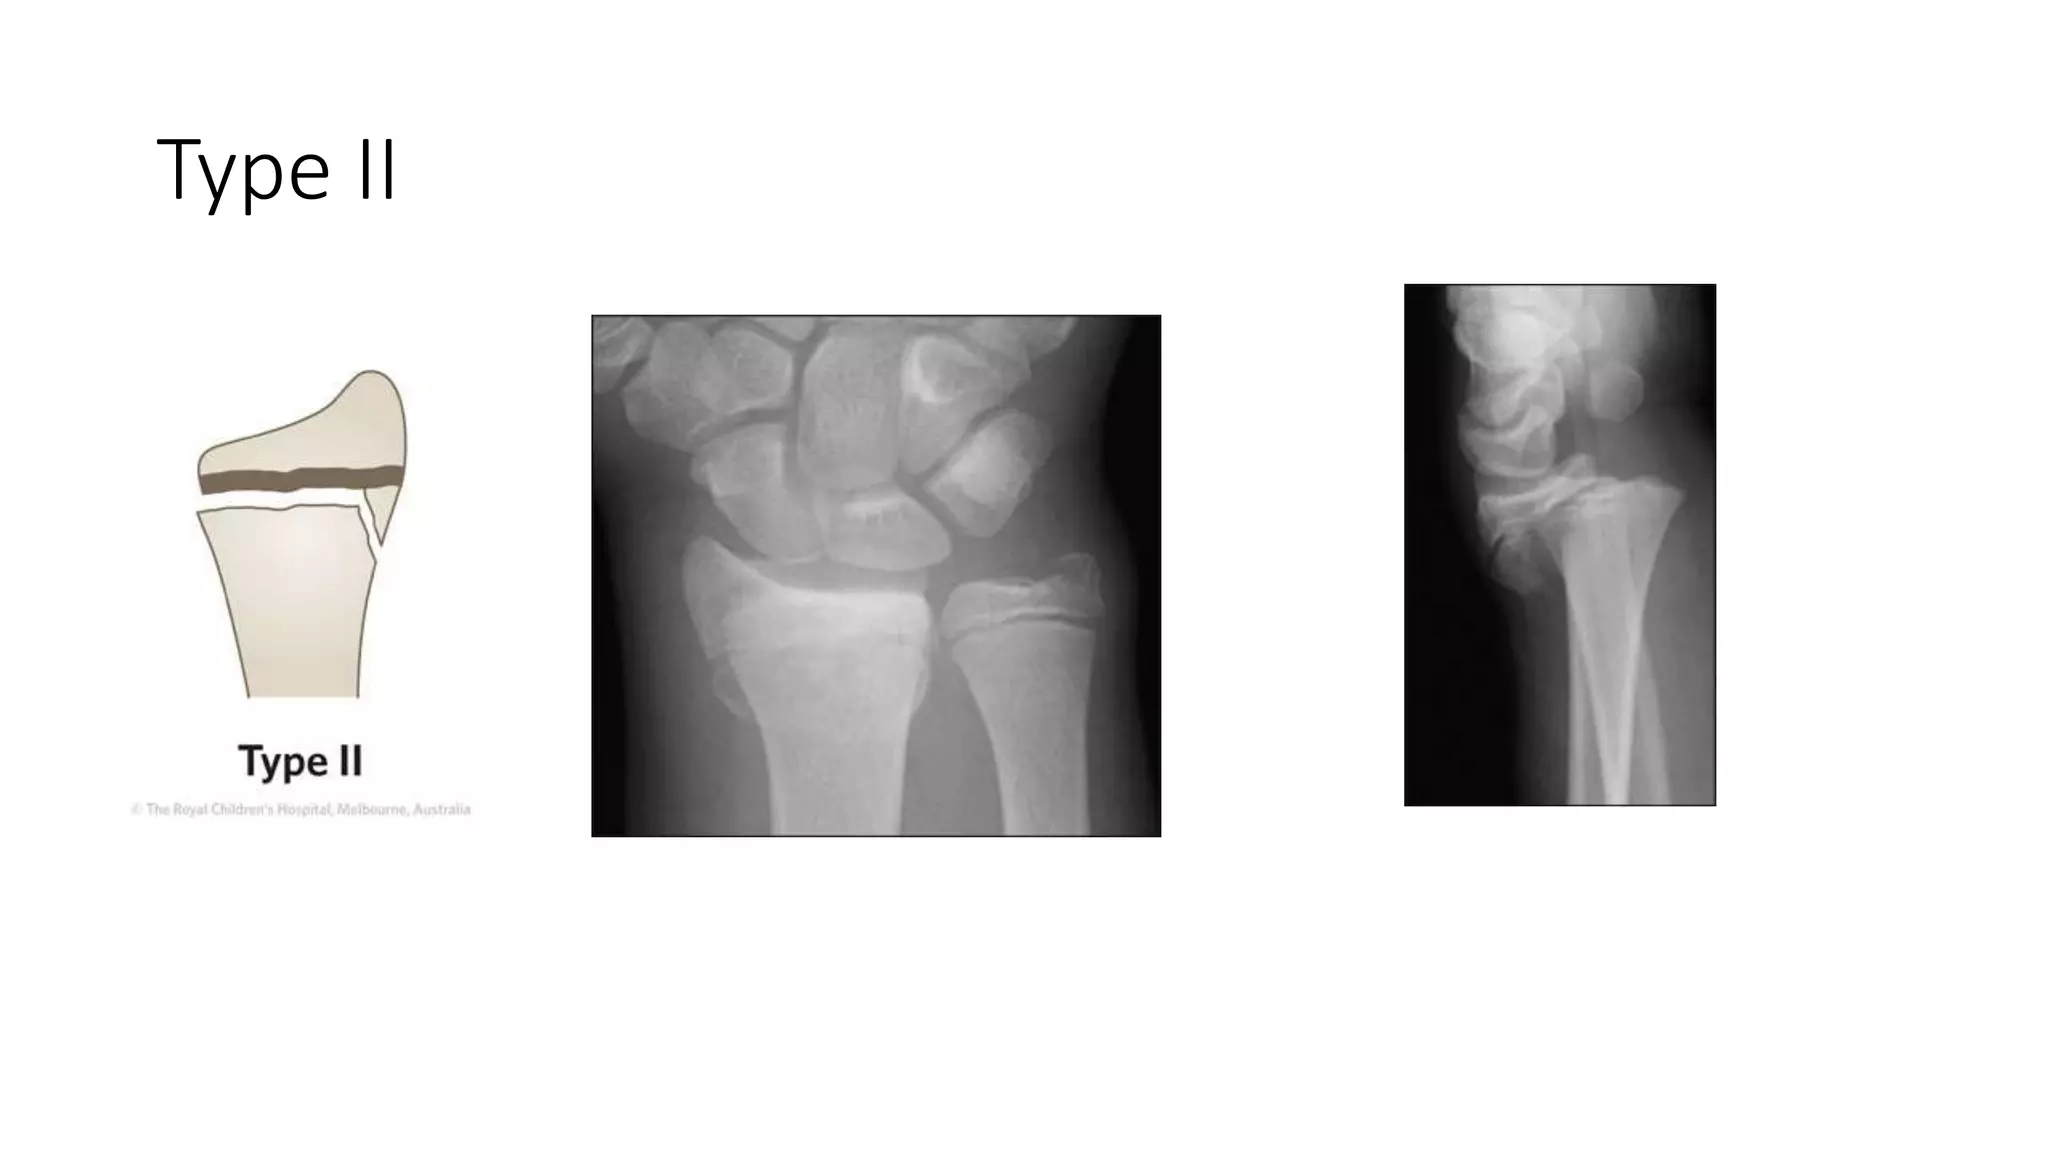

Fractures of the distal radial physis and barton's fracture | PPTX

Fractures of the distal radial physis and barton's fracture | PPT